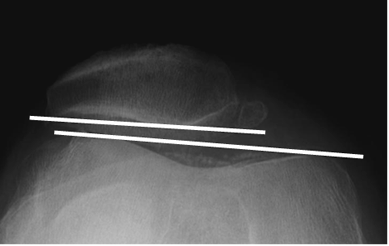

Rx tangencial de patela. Angulo patelofemoral anormal, con líneas paralelas, que indican desplazamiento lateral.

Fig 165 A. Inestabilidad patelar transversal.

A: Rx lateral y B: Rx tangencial. Cambios degenerativos con disminución del espacio patelofemoral, esclerosis y formación de osteofitos.